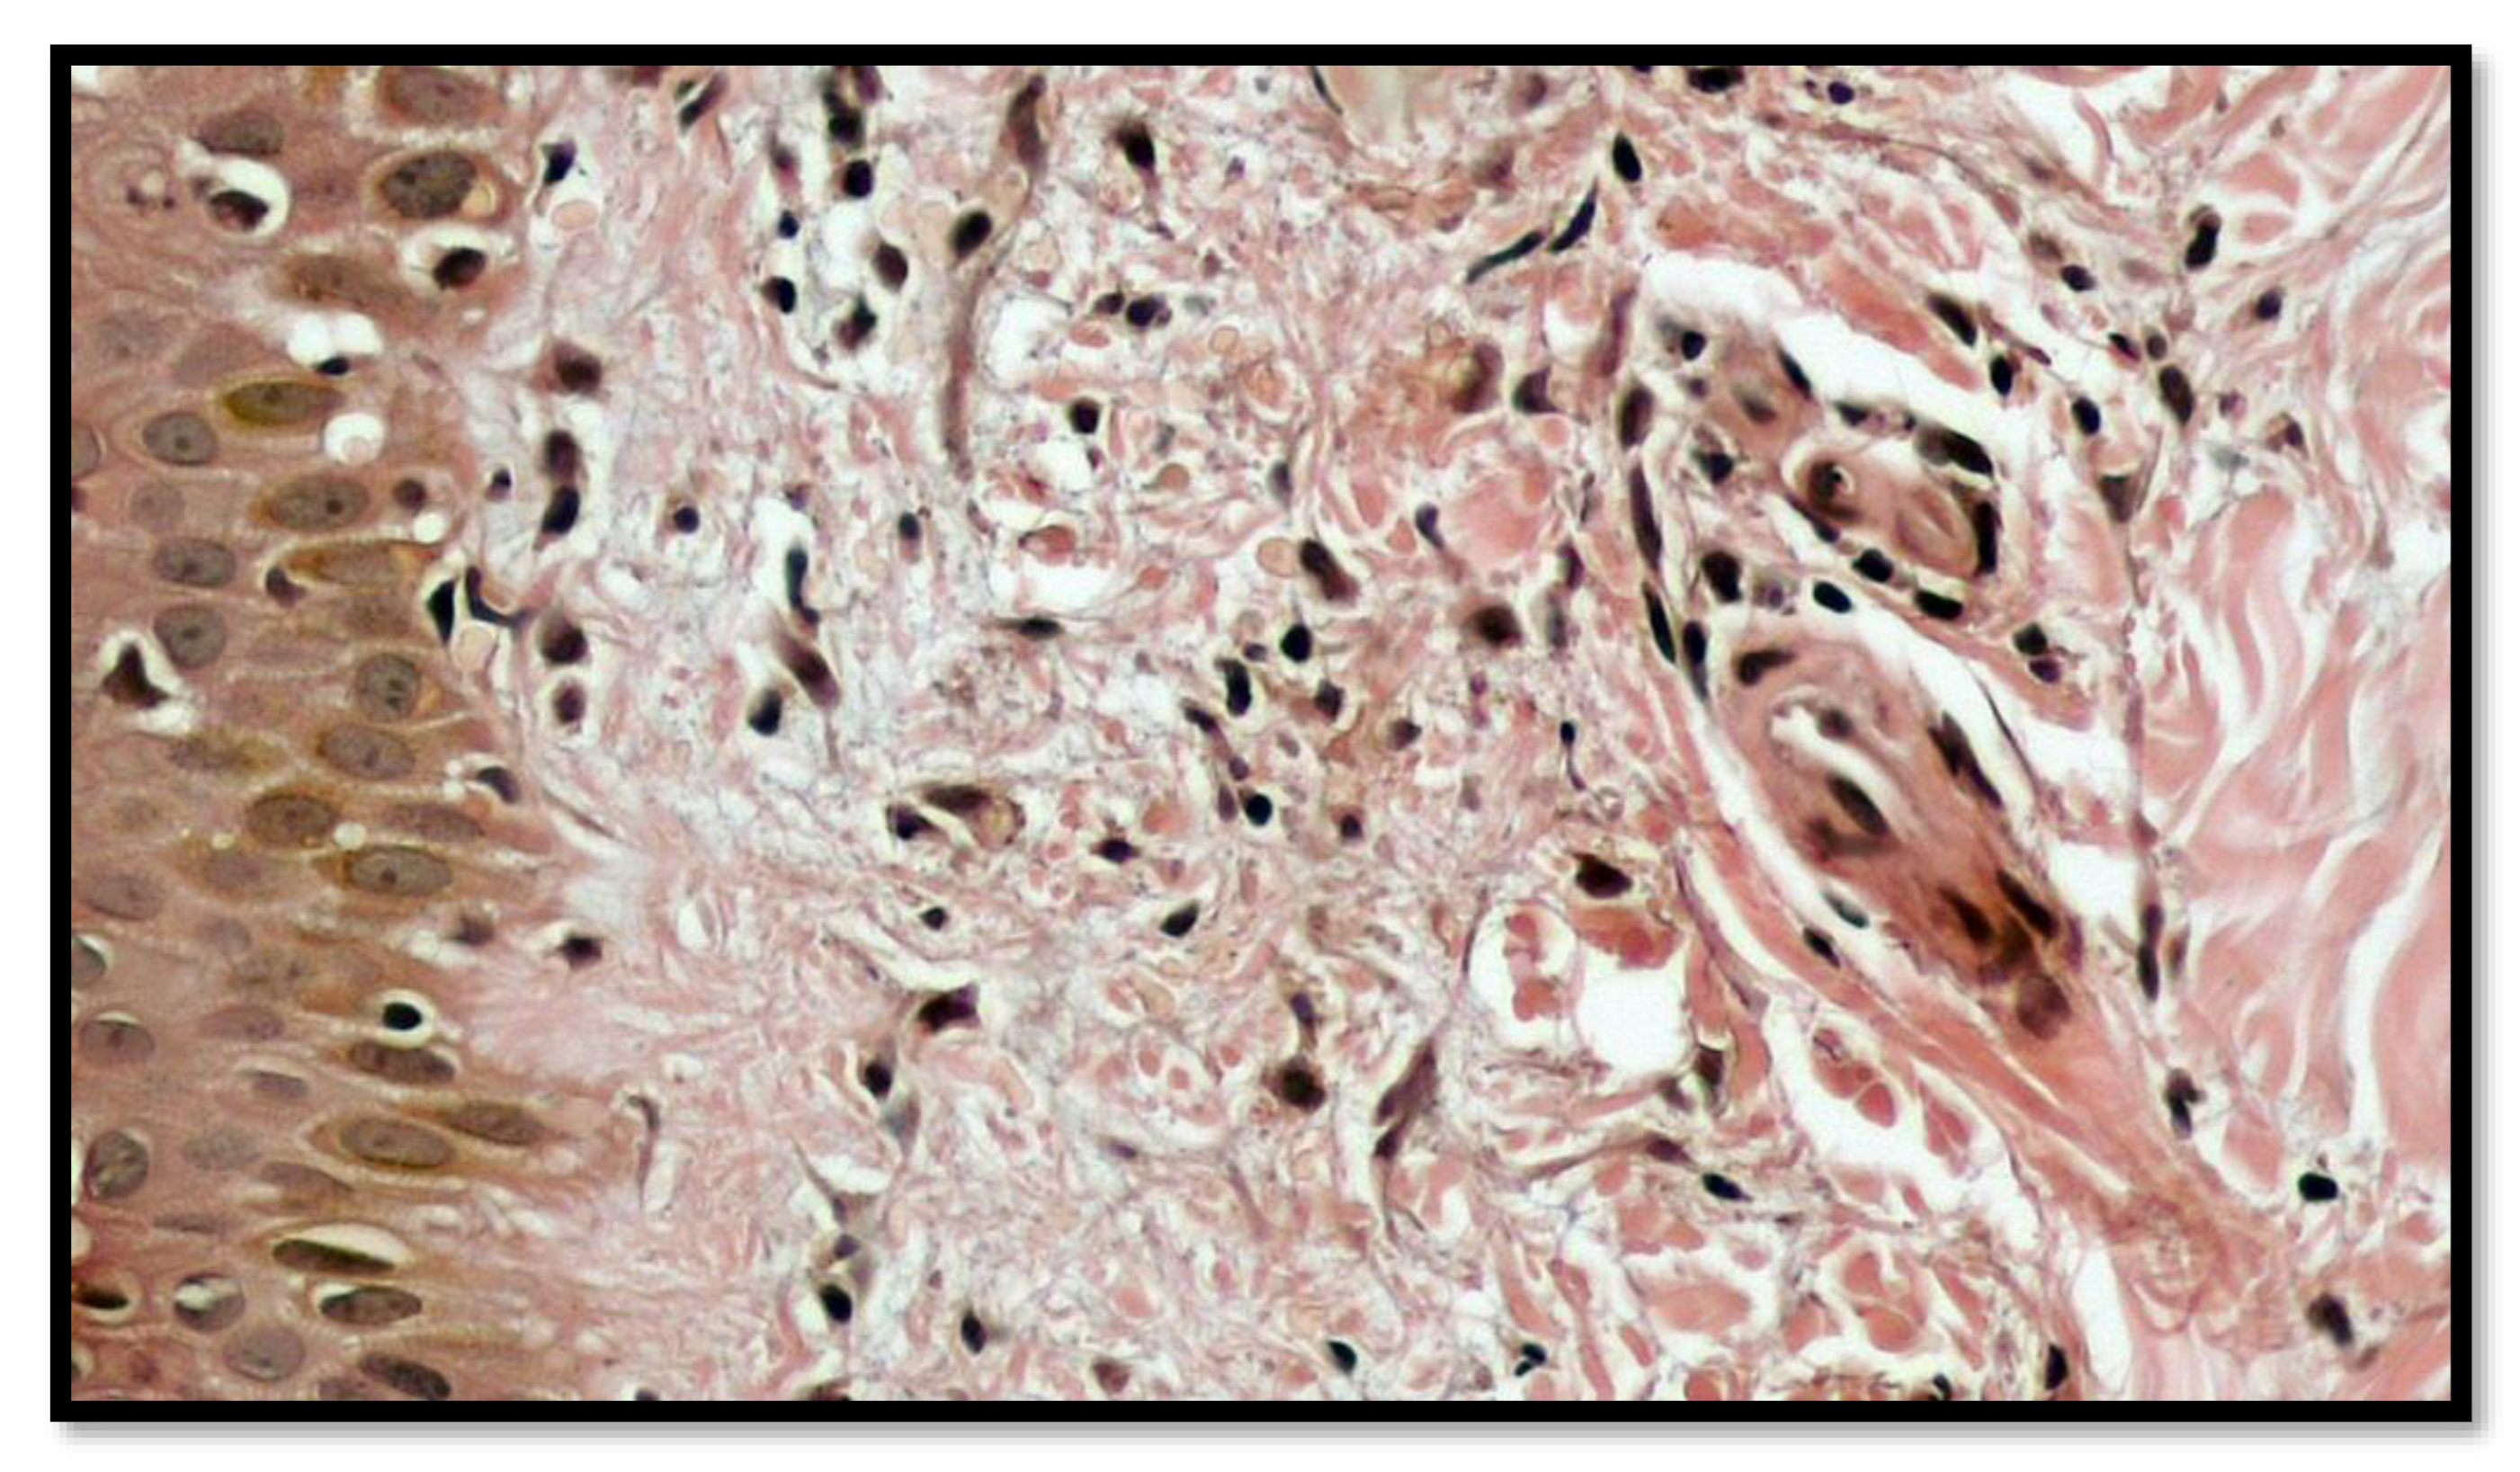

2. Case Report